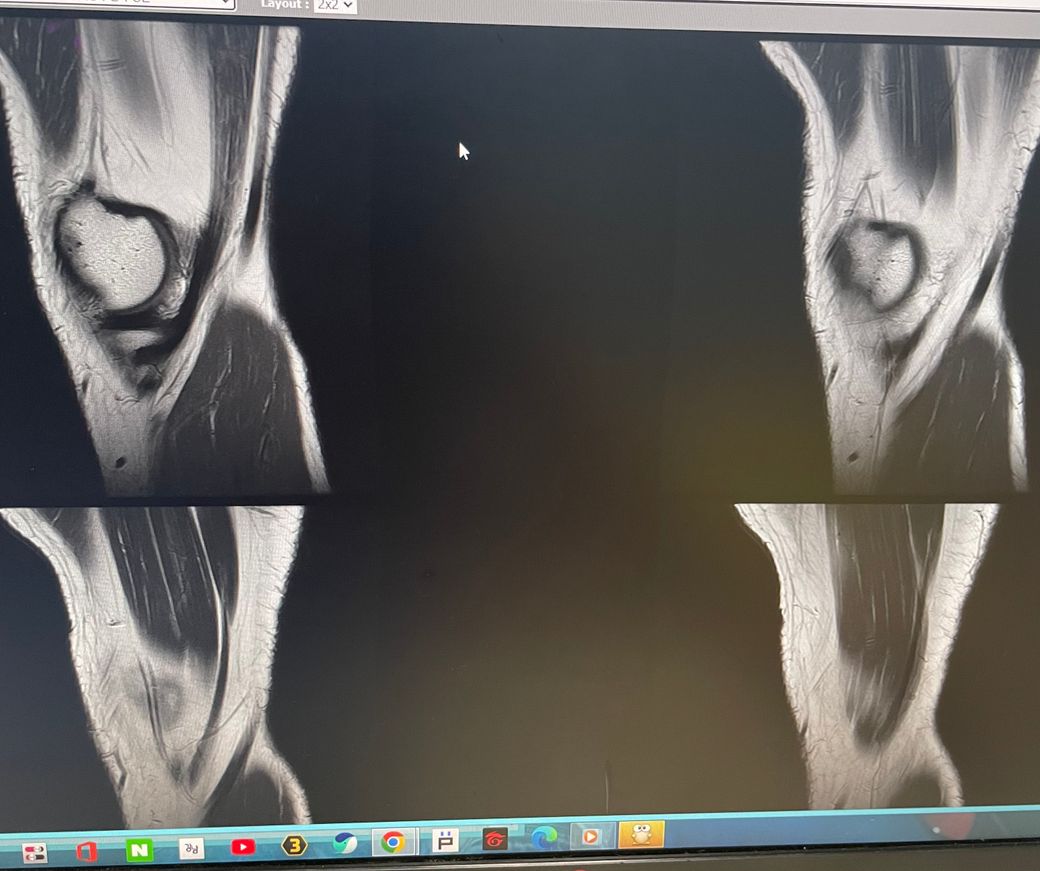

무릎 왼쪽 mri 사진 판독 부탁드리겠습니다.

안녕하세요 3달전쯤에 무릎을 다쳐서 약 한달전에 mri를 찍었습니다.

현재 판독상 인대나 반월연골 손상은 없는 것으로 판독지에 기재되어 있습니다. 임상적인 증상도 중요하니 담당의사와 상의하시고 신검시에 해당과 군의관 판정을 받으시는 것이 좋겠습니다.

ACL 즉 전방 십자 인대에 불규칙한 소견은 있으나 Tear 즉 십자 인대가 파열되었다는

소견은 관찰되지 않는 상태이며 연골에 퇴행성 변화는 있는 것으로 보이나 이 역시 R/O

으로 확실하지 않음을 의미합니다. 결과적으로 십자 인대의 파열이 명확하지 않는 상태로

군대를 연기할 사유가 될지는 모르며 전방 십자 등 인대 손상의 경우는 명확하게 파열된

소견을 보이지 않는 경우, 군 입대에 문제가 되지는 않을 것으로 생각됩니다.